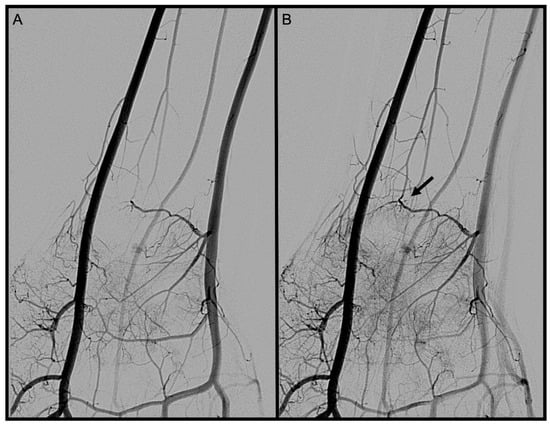

3.2. Dorsal Carpal Branch of the Ulnar Artery (DCBUA)